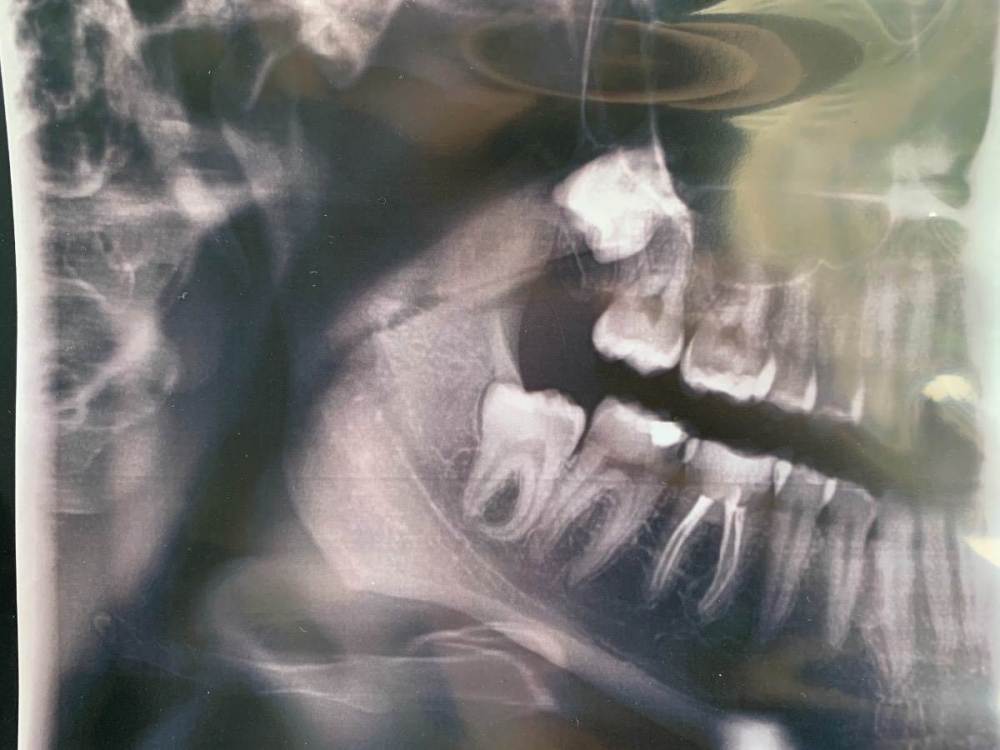

Mary189 Опубликовано 9 мая, 2022 Поделиться Опубликовано 9 мая, 2022 Здравствуйте уважаемые врачи. Уже на протяжении нескольких дней беспокоят периодические боли в области 7,6,5 зубов на нижней челюсти. Какой конкретно зуб непонятно, боль ноющая, давящая, не сильная, появляется и проходит в течении дня. При сжатии челюсти боли нет. Так же начала прорезываться восьмерка, судя по десне. Может ли она давать такие боли? Критична ли ситуация по снимку? Можно ли как то отложить поход к врачу? Ситуация осложнилась тем, что к стоматологу попасть в ближайшее время не смогу, попала неожиданно в больницу, возможно предстоит операция. Ссылка на комментарий

wladdX Опубликовано 9 мая, 2022 Поделиться Опубликовано 9 мая, 2022 Если судить по снимку и описанию, наиболее вероятный виновник зуб 47 (7-й внизу справа) Визит лучше не откладывать, может расшалиться "будь здоров" 1 1 Ссылка на комментарий